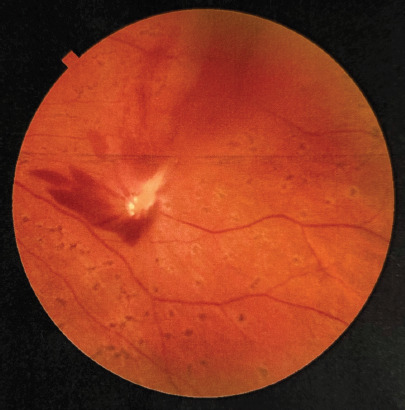

Figure 3

Optical coherence tomography examination of the left eye on the day of admission, showing the site of retinal injury with vitreoretinal junction and disruption of the neurosensory retina was visualized